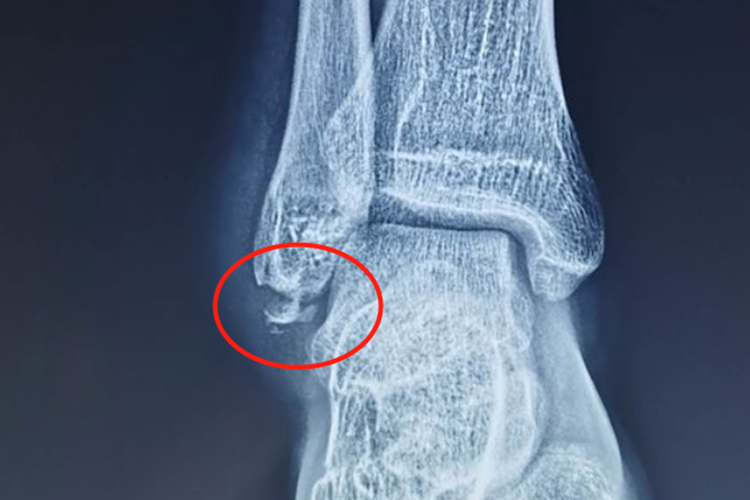

腓骨远端位于踝关节外侧,常因跌倒、坠落等外力作用导致腓骨远端撕脱性骨折,影像学可见腓骨远端异位,留有细小骨片。

腓骨远端撕脱性骨折表现为踝关节肿胀、畸形,存在异常活动,外踝压痛明显,皮下出血以及踝关节活动明显受限。影像学可见腓骨远端有横向骨折线,下部有一小块撕脱的骨片。